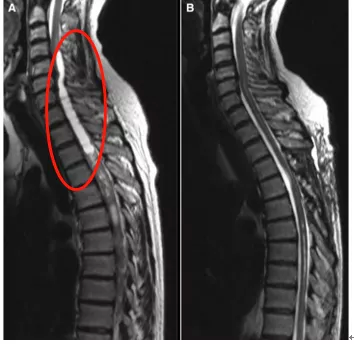

发现肿瘤连续累及颈髓、胸髓6个节段,同时伴有颅骨和延髓尾侧的空洞(图A)。这样病变范围广的病例,临床中少见,手术也是难度较大手术风险高。

较终完全切除肿瘤,无神经功能损伤,病人术前的双手麻木,进度疼痛好转、憋胀感消失、行走正常。3个月后复查空洞也几乎完全消失(图B),这台手术成功!

图:(A)T2 MR显示肿瘤连续累及颈髓、胸髓6个节段,同时伴有颅骨和延髓尾侧的空洞。(B)肿瘤完全切除后3个月的核MR显示空洞几乎完全消失。